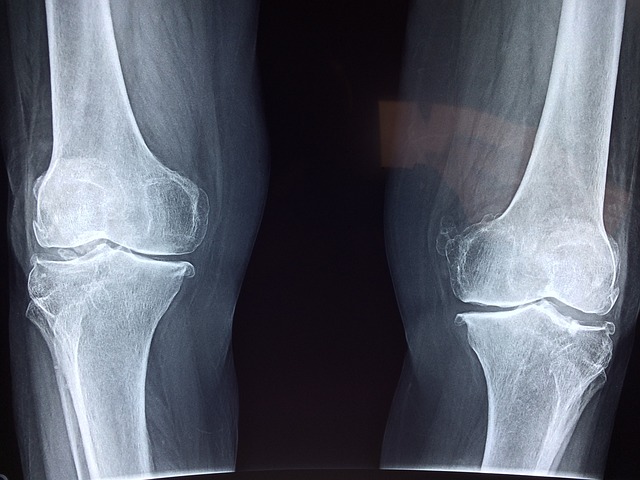

관절염

관절염은 관절에 염증을 일으키는 만성 질환입니다. 골관절염, 류마티스 관절염 및 통풍을 포함하여 무릎 관절에 영향을 줄 수 있는 여러 유형의 관절염이 있습니다. 관절염은 무릎 관절에 통증, 부기 및 뻣뻣함을 유발할 수 있습니다.